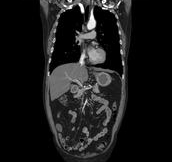

Body angiography with automatic bone and table removal - MIP reconstruction. Case: Aortic dissection. Left common iliac artery occlusion. Scanning: P0.83, 0.5s, 360mA, 100kV, weight 80kg, contrast 80cc

Body angiography with automatic table removal ? colored volume rendering reconstruction. Case: Aortic dissection. Left common iliac artery occlusion. Scanning: P0.83, 0.5s, 360mA, 100kV, weight 80kg, contrast 80cc